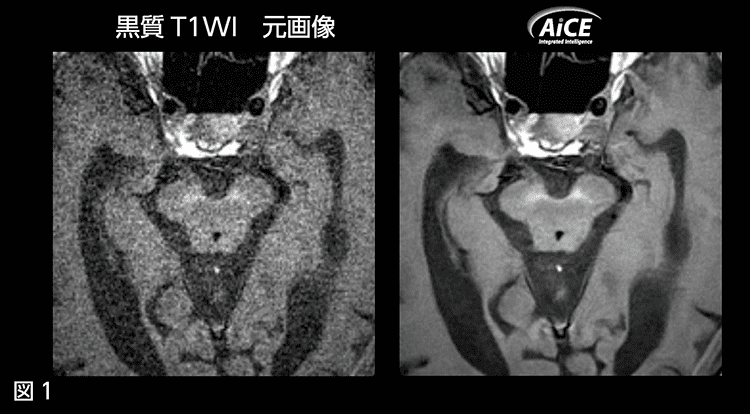

更新前の1.5T装置使用時に、神経内科から「黒質を描出してほしい」との要望がありました。しかし、黒質の描出には高分解能な画像が必要なため、従来のMRI装置では撮像時間が10分を超えるという報告もあり、ルーチンで使用することが難しい状況でした。

今回AiCEを導入したことにより、ノイズの多い高分解能画像であっても、コントラストを変えずにノイズのみを除去することが可能となりました。これにより、3分程度の時間で黒質画像(図1)を得ることができ、現在では神経内科のルーチンに含めて撮像するようにしています。